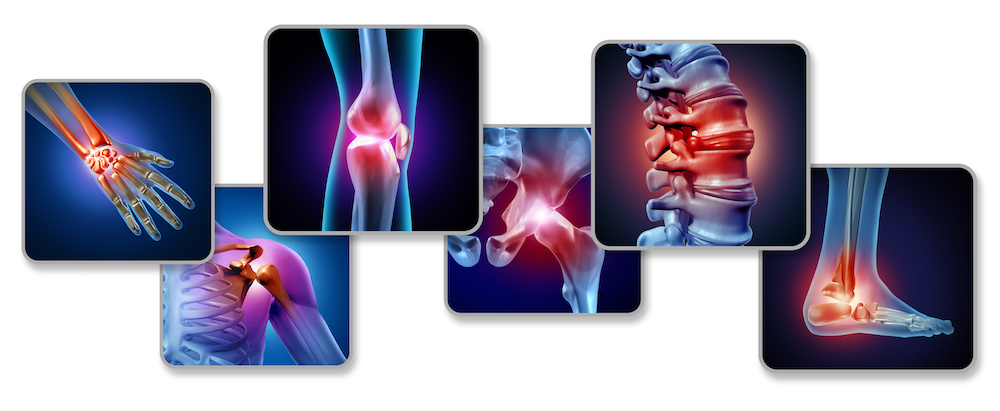

ارتوپد؛ این متخصص می تواند بیماری هایی مانند آرتروز، شکستگی استخوان، پارگی رباط ها، دررفتگی مفاصل و مشکلات ستون فقرات مانند فتق دیسک را درمان کند.

این متخصص می تواند بیماری هایی مانند آرتروز، شکستگی استخوان، پارگی رباط ها، دررفتگی مفاصل و مشکلات ستون فقرات مانند فتق دیسک را درمان کند. همچنین، این متخصصین در مدیریت آسیب های ورزشی، مانند پارگی رباط صلیبی قدامی (ACL) یا التهاب تاندون ها، تجربه گسترده ای دارند.

متخصص ارتوپدی بیماری ها و مشکلات متعددی را درمان می کند، از جمله:

- آرتروز: التهاب و تخریب مفاصل زانو، لگن یا شانه.

- شکستگی های استخوانی: شکستگی های ساده یا پیچیده در اندام ها.

- آسیب های ورزشی: پارگی رباط ها، التهاب تاندون ها یا آسیب های عضلانی.

- مشکلات ستون فقرات: درمان فتق دیسک، تنگی کانال نخاعی یا انحراف ستون فقرات (اسکولیوز) توسط ارتوپد ستون فقرات.